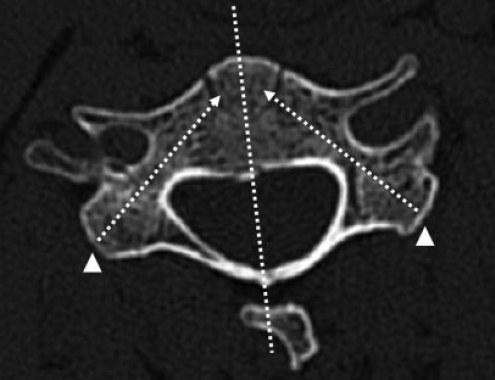

(2)俯卧位,常规后路显露,骨膜下剥离软组织至侧块关节外缘。于侧块关节内缘与椎板交接开窗,探查椎弓根内壁。(以C5右侧CPS螺钉置入为例,右侧为头端)

(3)经开窗根据神经钩探查的椎弓根内壁位置,在直视下置入CPS。

(4)术中全程无透视完成置钉,术后复查CT观察CPS螺钉位置。本例与术前规划一致,白色三角形箭头所示两侧探查椎弓根于椎板开窗位置。